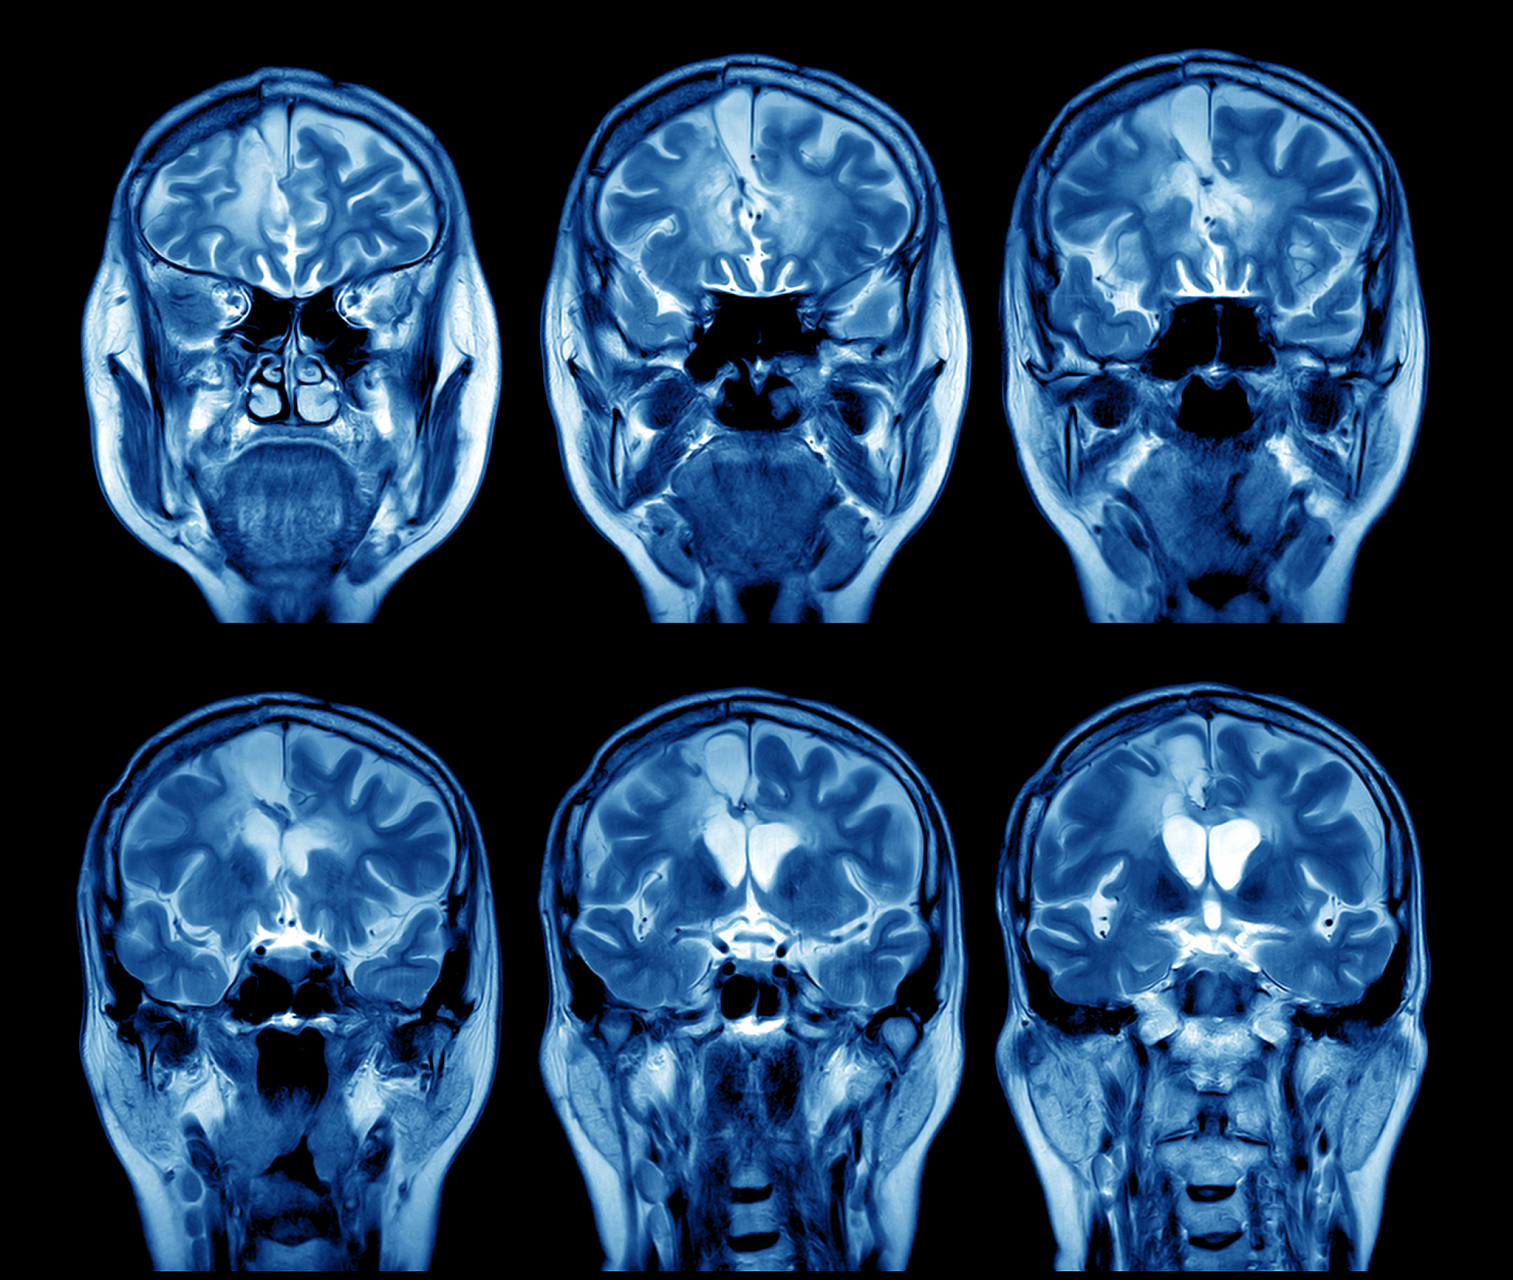

mri脑部影像

这可能是全网最高清的离体人脑mri扫描图像/医学资料

新生儿大脑的磁共振成像